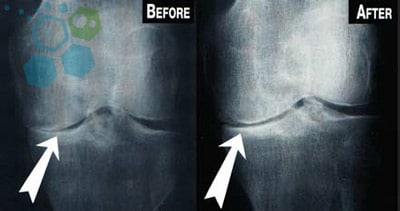

Degenerative Osteoarthritis of the Knees

Knee Meniscus Tears & Cartilage Loss

Cell Regeneration for Knee Pain after Cartilage Loss